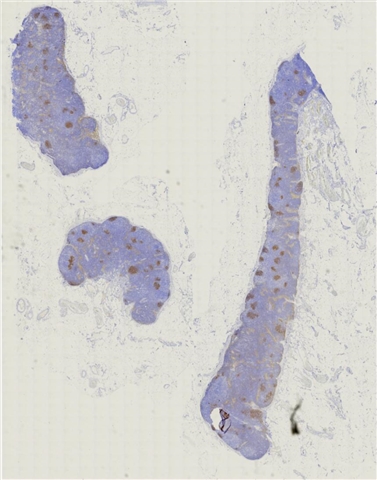

案例3 (7164)

性别:       年龄:19

患者详情: 发现颌下肿块1月,B超检查示颌下腺区域异常低回声,未见淋巴门结构,大小42*23mm,内部见较丰富血流信号,造影均匀等增强,NHL待排。行肿块穿刺活检。全身检查无肿大淋巴结。

大体所见: 巨检:条索状碎组织0.7*0.3*0.1cm。

医院: 复旦大学附属华东医院